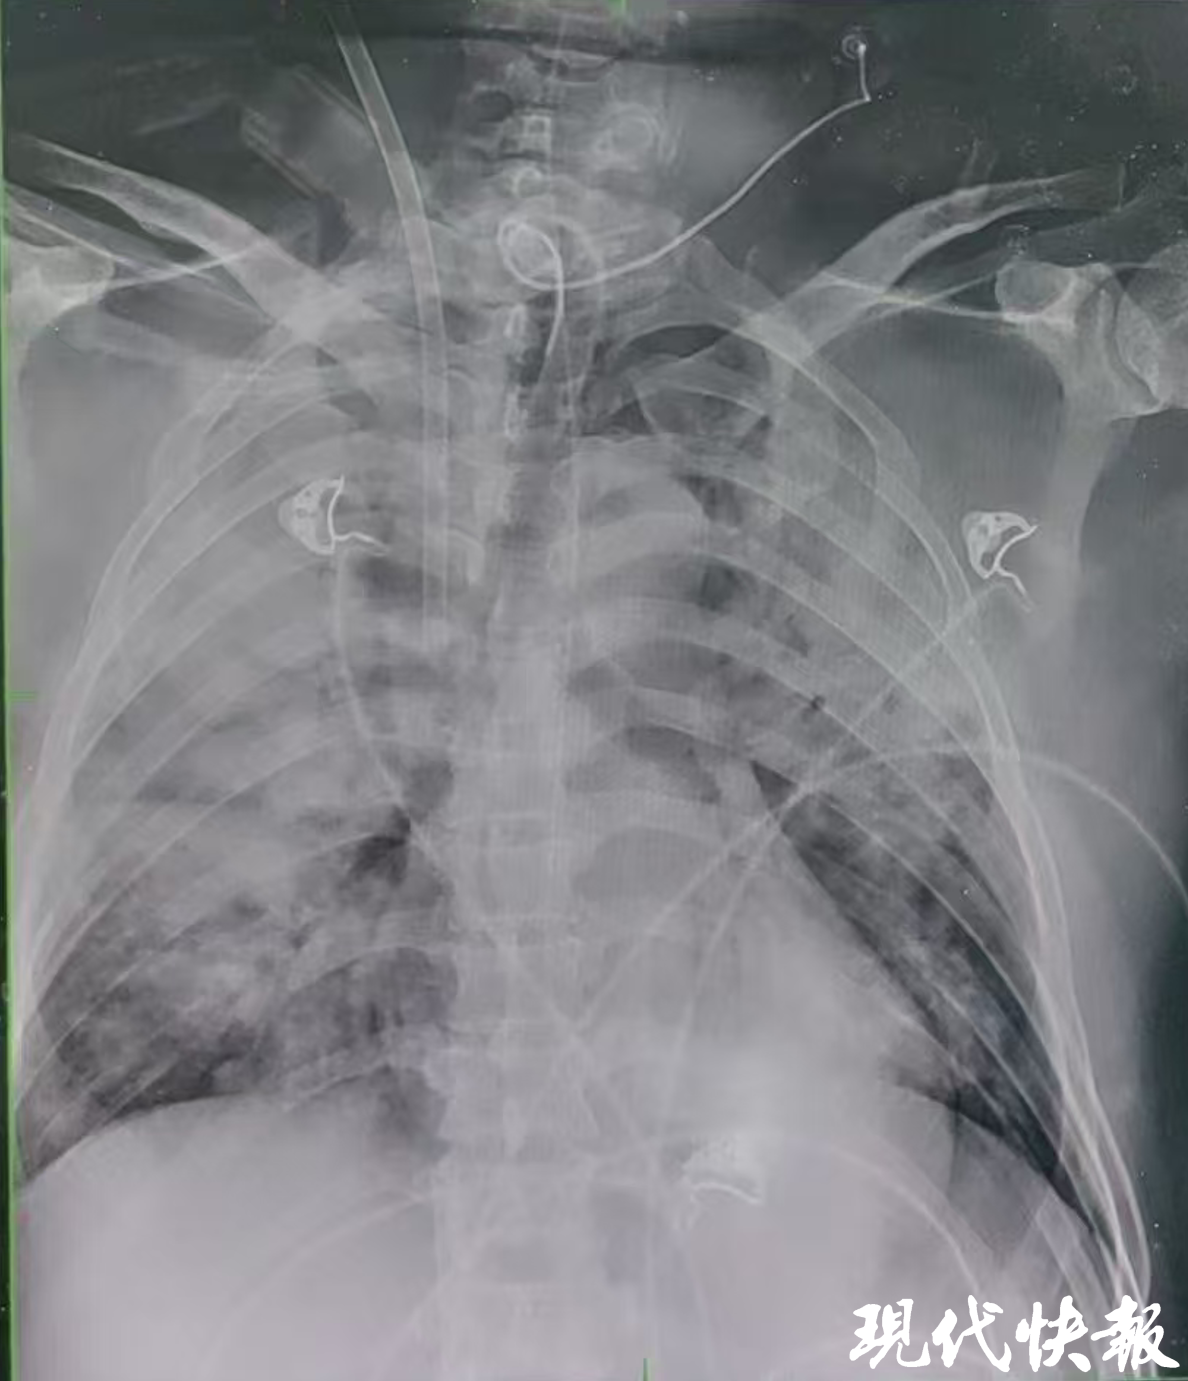

小足癣惹大祸,女子小腿染“毒”!武汉两院专家联手带她脱险极目新闻 昨日 -